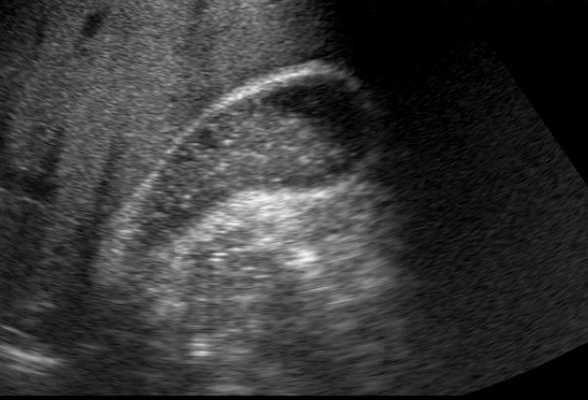

Сладж желчного пузыря - это густая вязкая желчь, которая состоит из кристаллов моногидрата холестерина, гранул билирубината кальция, внедренные в матрицу гелеобразной слизи из гликопротеинов. Он часто развивается у больных при длительном голодании в отделениях интенсивной терапии, травматологических больных, получающих полное парентеральное питание, и в течение от 5 до 7 дней при голодании у пациентов, которые перенесли операции на желудочно-кишечном тракте. Билиарный сладж обычно имеет волнообразное течение и на УЗИ может исчезать и появляться в течение нескольких месяцев или лет. Сладж может быть промежуточным этапом в формировании желчных камней. Около 8% пациентов с признаками билиарного сладжа будут иметь бессимптомные желчные камни.

На УЗИ по нашим данным в Красноярске, данная патология производит гипоэхогенные, не дающие тени эхо сигналы, которые, как правило, имеют слои в наиболее расширенной части желчного пузыря. Сладж на ультразвуковом исследовании движется медленно, когда пациент меняет позиции. Агрегированные сгустки желчи могут быть мобильными и не дающие тени, иногда с содержанием гиперэхогенных, внутрипросветных масс или как кашицеобразных полиповидных образований в зависимой части желчного пузыря. Желчный пузырь, полностью заполненный сгустками желчи может быть изоэхогенным к прилегающей ткани печень и его бывает трудно определить по УЗИ, поэтому данное состояние называют опеченение желчного пузыря. Мелкий песок тоже отличаются по внешнему виду от мелких камней тем, что он также гиперэхогенный, но не отбрасывает акустическую тень. С другой стороны, густая желчь при слажде более вязкая, прилипает к стенкам пузыря и не имеет явную гравитационную зависимость как песок или камни желчного пузыря.